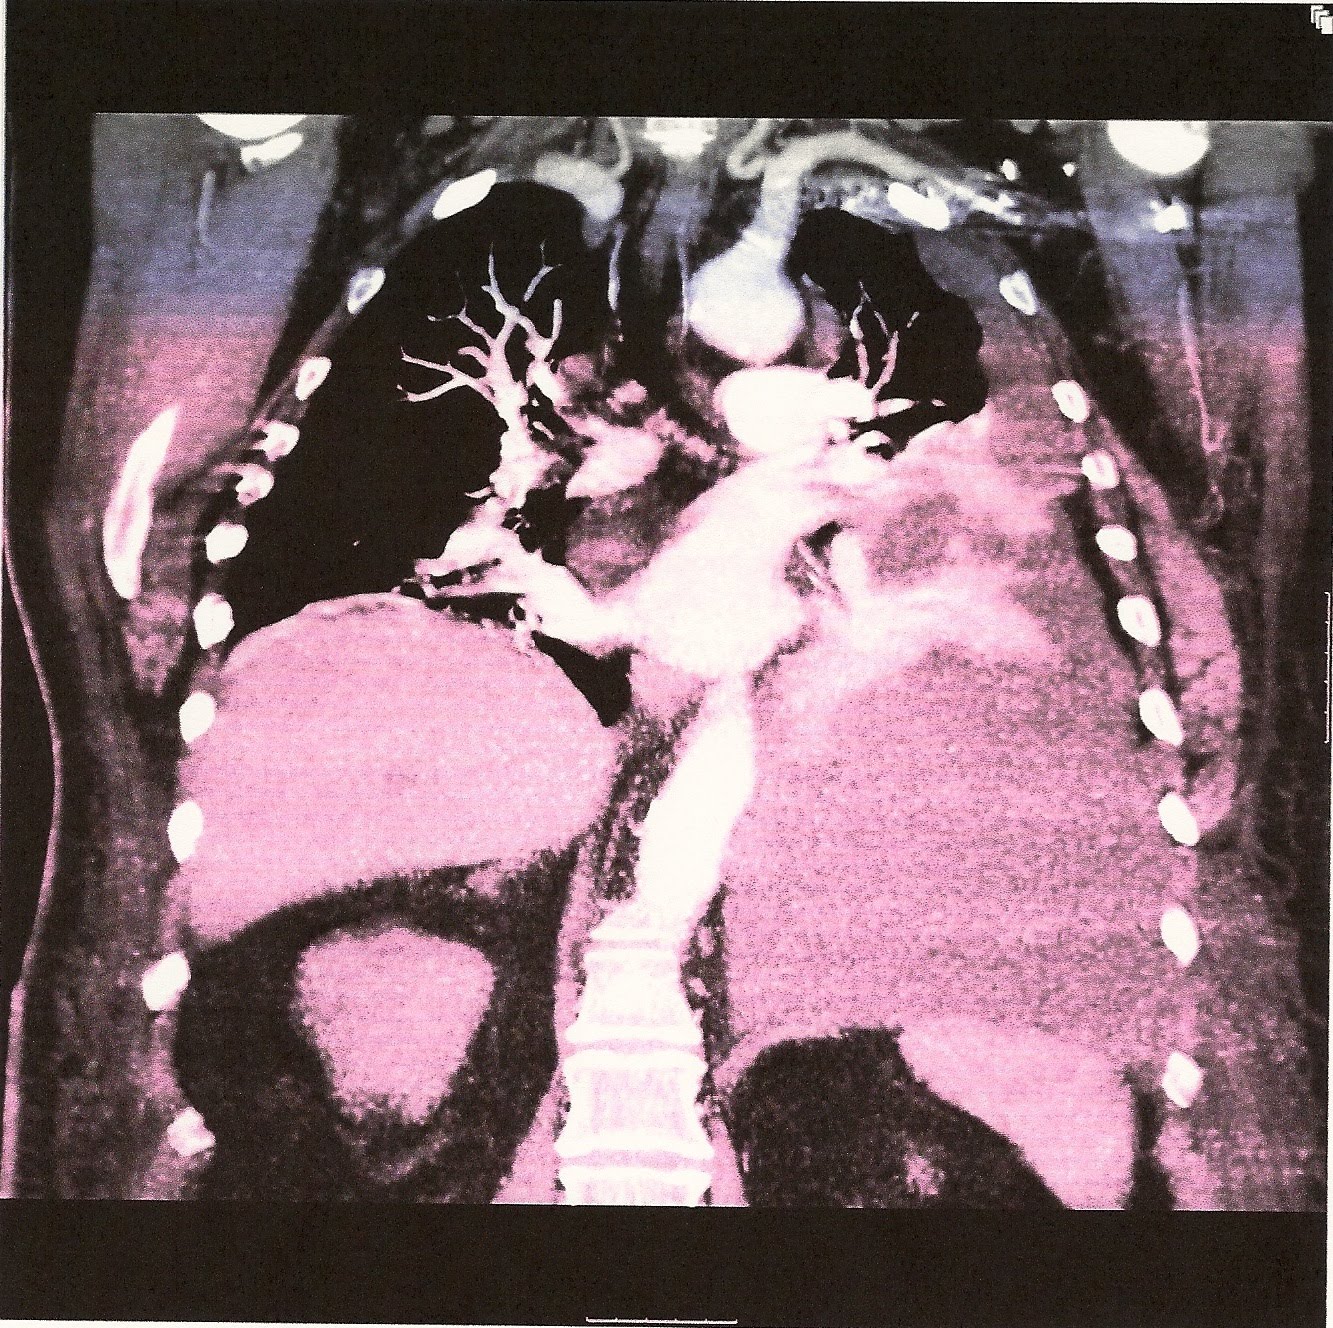

This patient had a chest surgery about two months prior to this CT. He was sob but not severe. He complained of abdomen fullness which I ignored.

hemothorax is right and right system --clue you will not be able to see the cause of the problem but must think about a surgery that could cause it. That is the key to the whole exercise.

So this individual had a CABG and subsequently developed a hemothorax. Great case. Did he require a chest tube or was thoracentesis sufficient?

1st thoracentesis 4 liters of old liquid blood! And much improvement of his symptoms. Another 3 liters removed 2 weeks later. The plan is to continue to monitor his symptoms. Now looking at cxr and old fashion auscultation and percussion. As you will see in the subsequent post many CABG pts have pleural effusions not many have large effusions but most are managed by observation and thoracentesis.